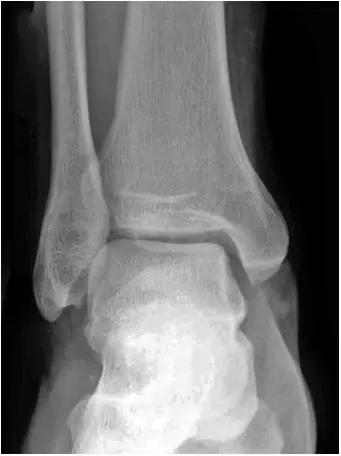

2、影像学表现:

- 踝关节正侧位X 线平片,侧位片均显示距骨后方有三角形或椭圆形的距后三角骨。部分病例伴有轻度的踝关节骨性关节病。

- MRI 检查示距后三角骨及周围软组织有水肿信号,距后三角骨和距骨之间正常的低信号纤维连接中断,出现液性信号。